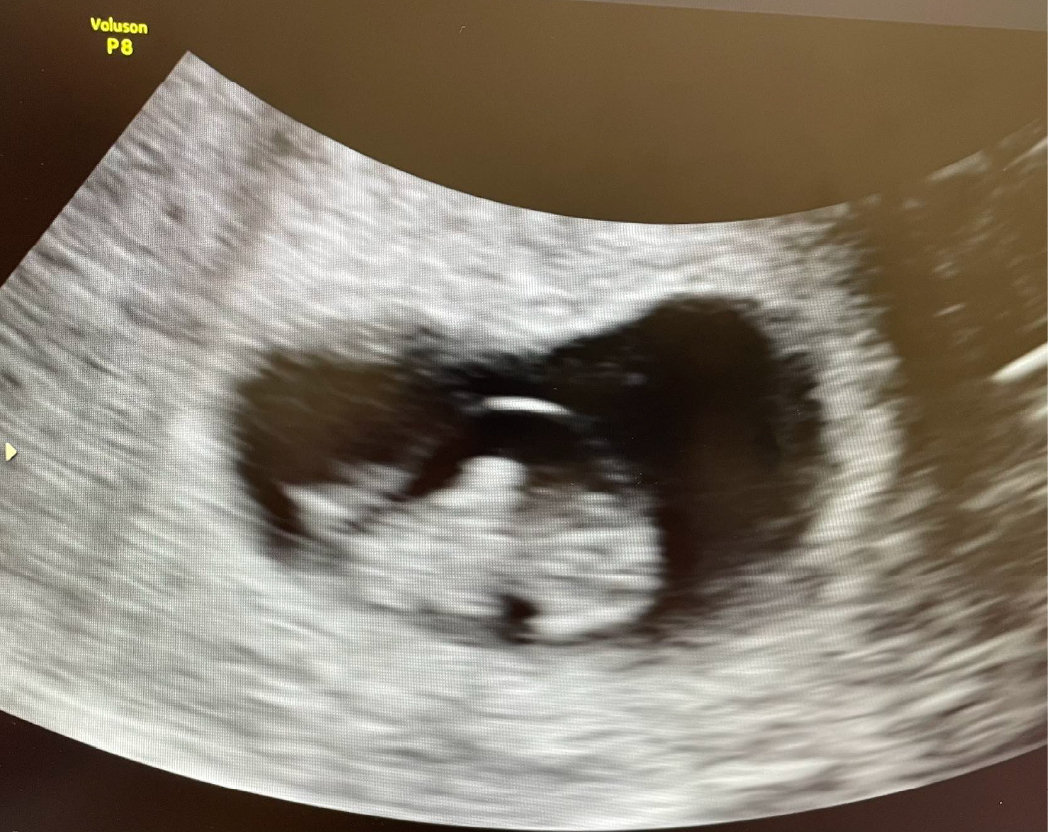

8+周胎心跳及胎兒活動力都好棒棒💕